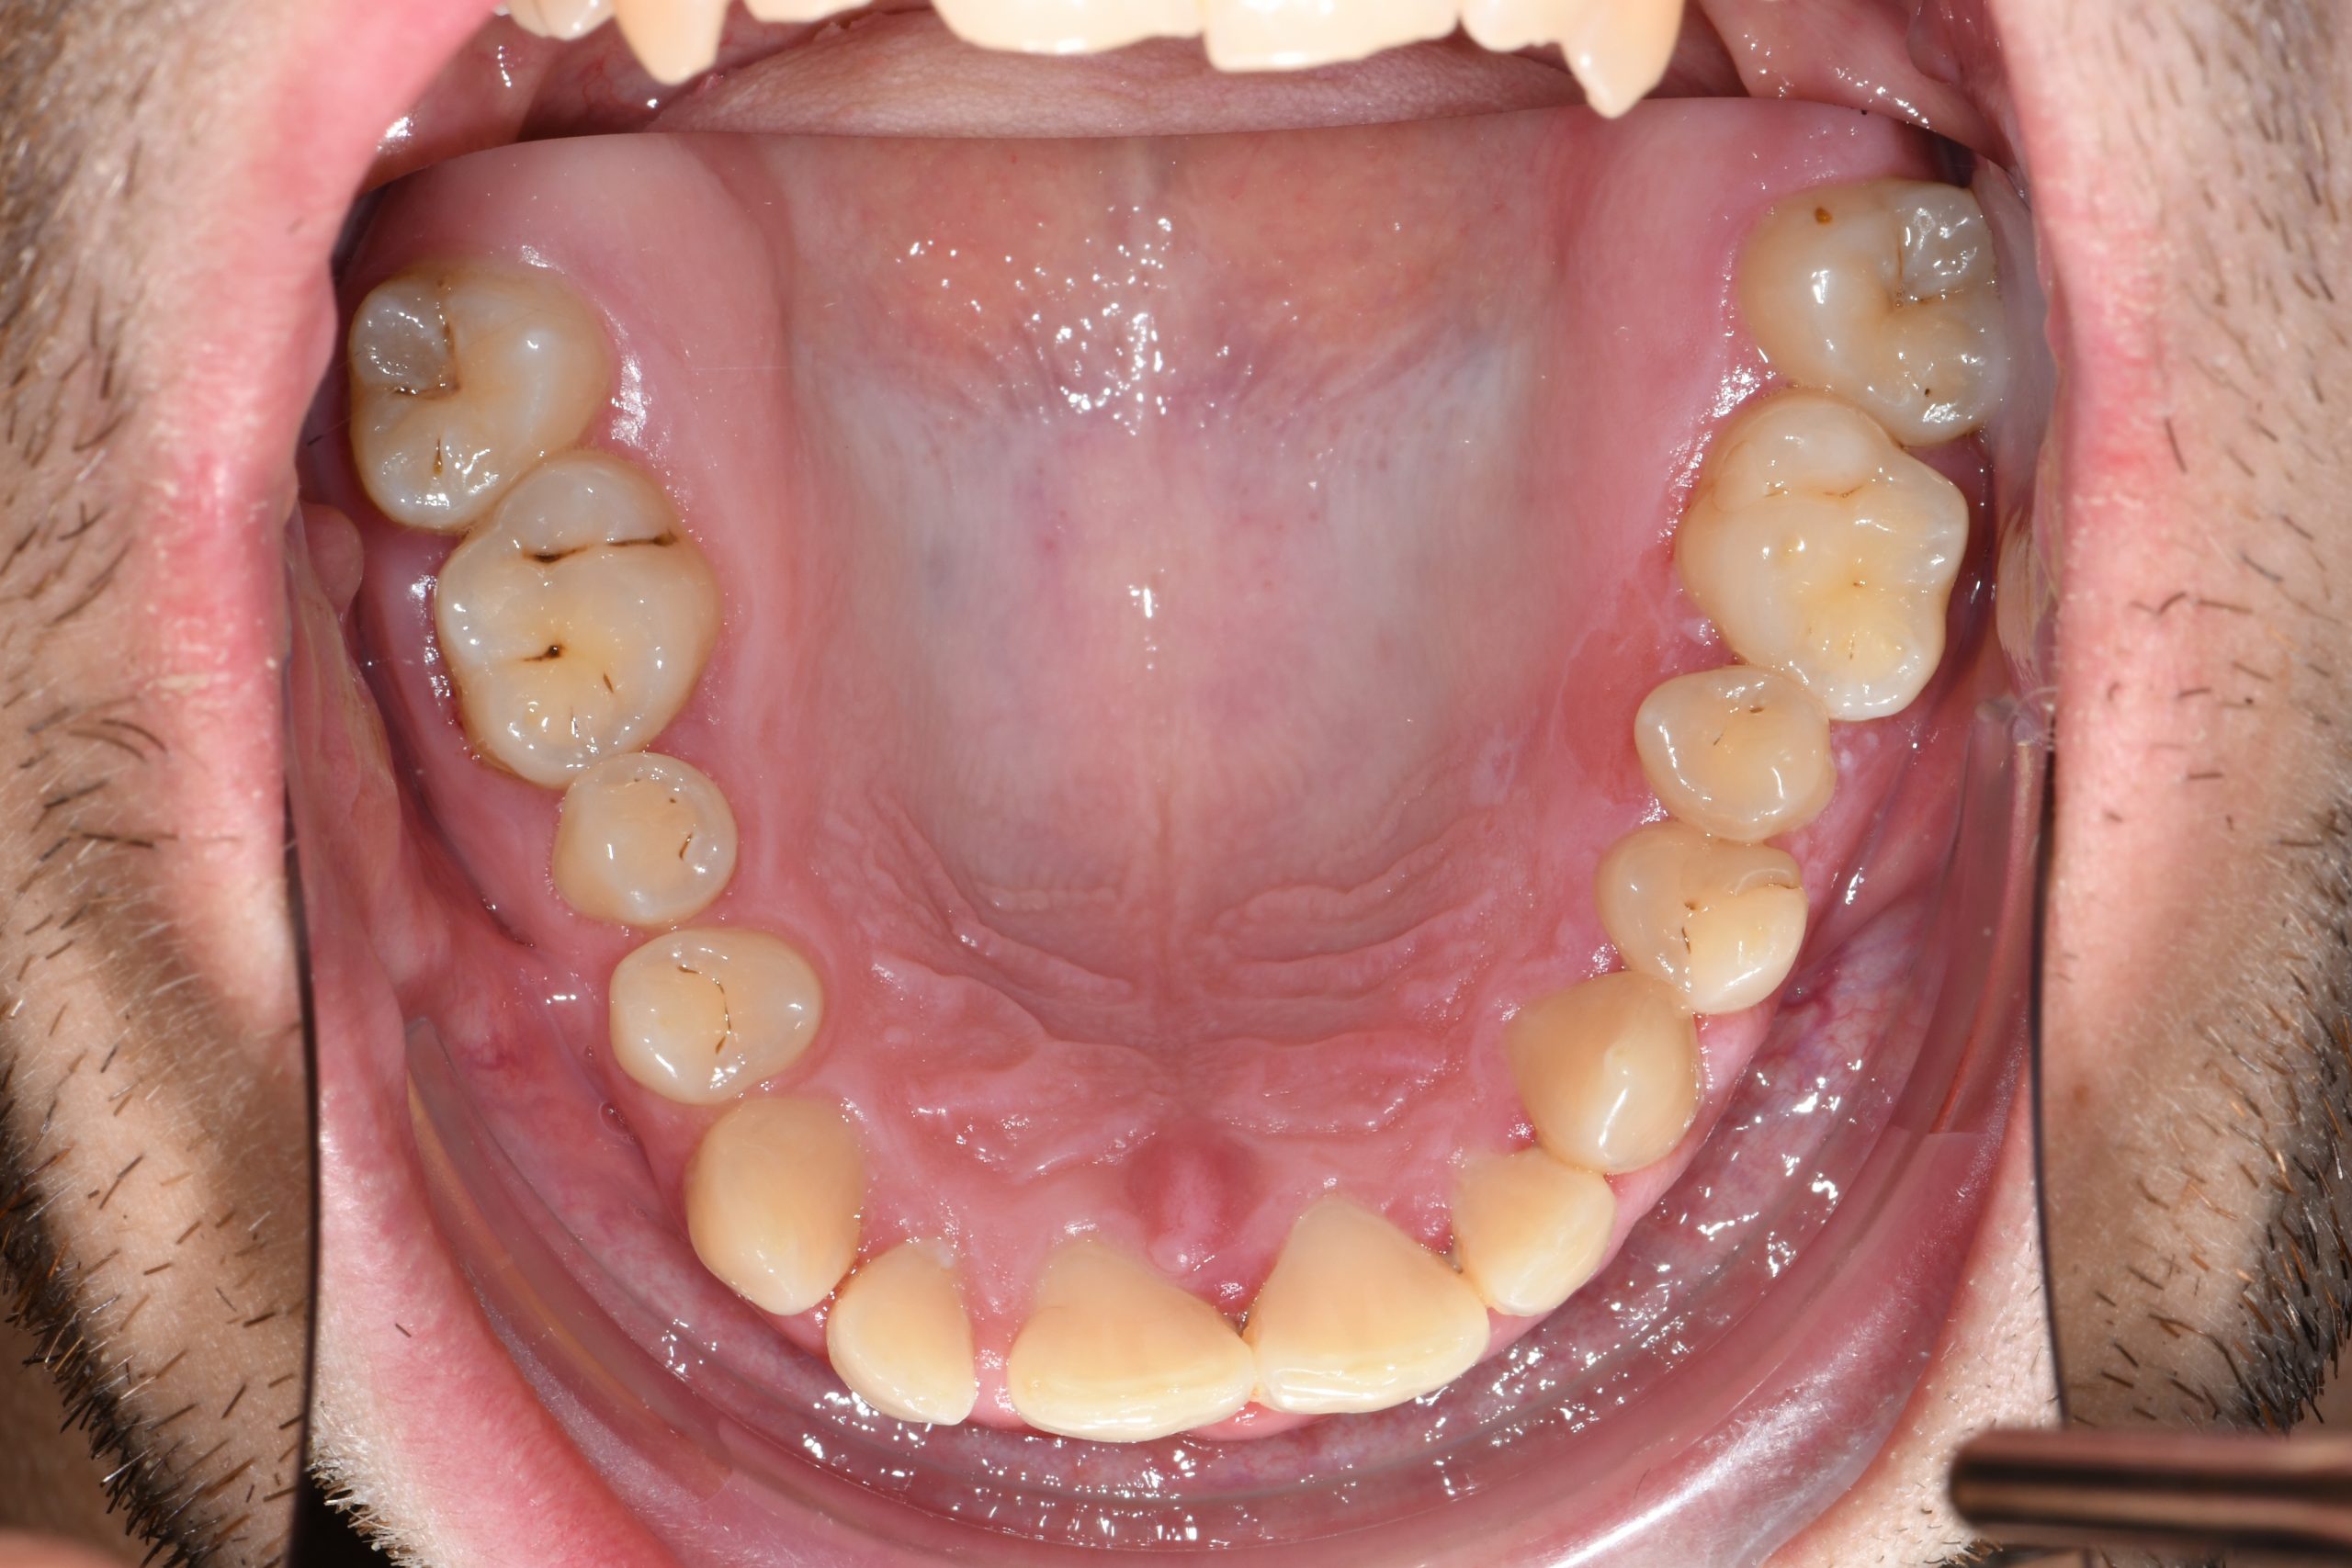

Az elmúlt évekből rengeteg szakmai referenciát tudnánk bemutatni, amelyek különböző fogszabályozási problémákat oldottak meg. Válogatva a több száz esetből, ezen az oldalon olyan képeket, információkat igyekeztünk bemutatni, amelyeknek a segítségével a jövőbeni pácienseinknek azt tudjuk üzenni: A Te fogsorod is lehet gyönyörű!

(Képeket a Pácienseink külön írásos beleegyezésével mutatjuk be!)